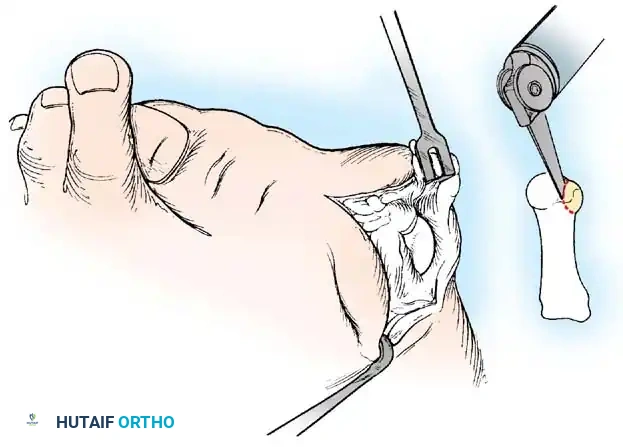

• Resect the medial eminence at the sagittal groove, beginning dorsally at its distal edge and directing a 9-mm oscillating blade

(or osteotome) plantarward and slightly medially (5 to 10 degrees).

• Remove the base of the proximal phalanx at the metaphysealdiaphyseal junction, which usually constitutes the proximal third of the phalanx (Fig. 78-30A and B). To prevent damage to the fl exor hallucis longus and the neurovascular bundles, place a retractor over the bone dorsally and plantarward, and rotate the phalanx into view. Also, do not allow the saw blade to exit bone more than 1 to 2 mm.

• When the osteotomy has been completed, grasp the basilar fragment with a small Kocher clamp or towel clip, and rotate the fragment while applying medial pull to excise it. Lift it away from its lateral attachments, which are primarily the lateral collateral ligaments and the adductor muscle tendinous insertion (Fig. 78-30C).

• With the ankle at 90 degrees, bring the hallux into a corrected position, while manually pushing the fi rst metatarsal as far laterally as possible. Evaluate the alignment, keeping the metatarsal and hallux straight.

A B

Fig. 78-30 Keller technique. A, Re section of proximal phalanx, release of adductor tendon, and resection of medial eminence. B, Metaphyseal-diaphyseal junction of proximal phalanx (arrow) . C, Note concave plantar aspect of proximal phalanx for course of fl exor hallucis longus tendon (arrow) .

• Grasp the hallux in one hand and displace the proximal remnant medially so that, under direct vision, two longitudinal 0.062-inch Kirschner wires can be inserted.

• Hold the interphalangeal joint straight while drilling the wires from proximal to distal, emerging a few millimeters plantar to the nail plate.

• Return the foot to the corrected position, and drill the wires into the metatarsal head.

• While holding the metatarsal as far laterally as possible, cross the joint, and drive the wires out the plantar cortex just proximal to the head, while holding the hallux in 10 to 15 degrees of extension, neutral abduction, adduction, and rotation, and no translation dorsally or plantarward on the metatarsal head. The wires should penetrate only 2 to 3 mm past the cortex to avoid tenderness over the wires with weight bearing.

• If the Kirschner wires tend to “walk” on the rounded articular surface of the metatarsal head, use a small hemostat snugged up against the wire while it is being drilled to allow accurate placement. Proper placement of the wires and the desired position of the hallux on the metatarsal may require several attempts. The medial aspect of the proximal phalanx should not rest medial to the medial aspect of the metatarsal head.

• Place the hallux in the neutral medial-lateral plane and in 10 degrees of extension.

• Before the second wire is driven into the fi rst metatarsal head, place the hallux in proper rotation, using the plane of the nail as a guide. The initial length of the hallux is maintained by the wires. Later, collapse occurs when the wires are removed, but improved encapsulation of the hemiarthroplasty, by maintaining length for the fi rst few weeks, may help maintain a more desirable position long-term.

• Cut the wires off 2 to 3 mm distal to the skin edge.